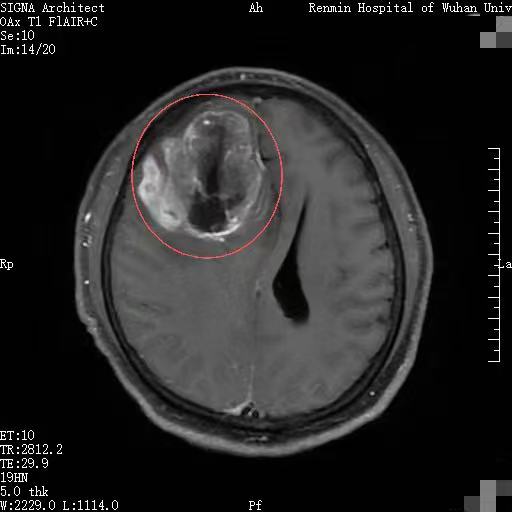

一个月前,湖北黄石市民李先生因持续半个月出现全身乏力、精神萎靡等症状,来到武汉大学人民医院东院区就诊。入住风湿免疫科后,颅脑核磁共振检查显示,其右侧额叶有一巨大占位,高度怀疑为恶性肿瘤。

更危急的是,巨大肿瘤会引发严重脑水肿,还伴有脑积水。此时,李先生颅内状况如同一颗被挤到极限的“炸弹”,随时可能危及生命。

李先生被紧急转入东院区神经外科四病区。刚转科不久,他就突发浅昏迷,一侧肢体偏瘫。急诊复查CT提示,其脑水肿较前显著加重,脑疝形成,生命体征告急。

“这是典型的颅内高压危象,肿瘤周围水肿急剧加重引发了脑疝。”神经外科四病区主任王峻教授团队当即采取抢救措施,暂时稳住病情。但唯有尽快手术切除肿瘤,才能从根本上解除生命威胁。

手术难度极大。王峻教授团队如“雕刻”般彻底切除病变组织,同时小心翼翼保护负责运动、语言等重要功能的脑区及关键血管。术后,患者受压移位的脑组织逐渐复位,颅内生命通道恢复通畅。影像学复查结果显示,肿瘤切除效果满意,脑疝完全复位。